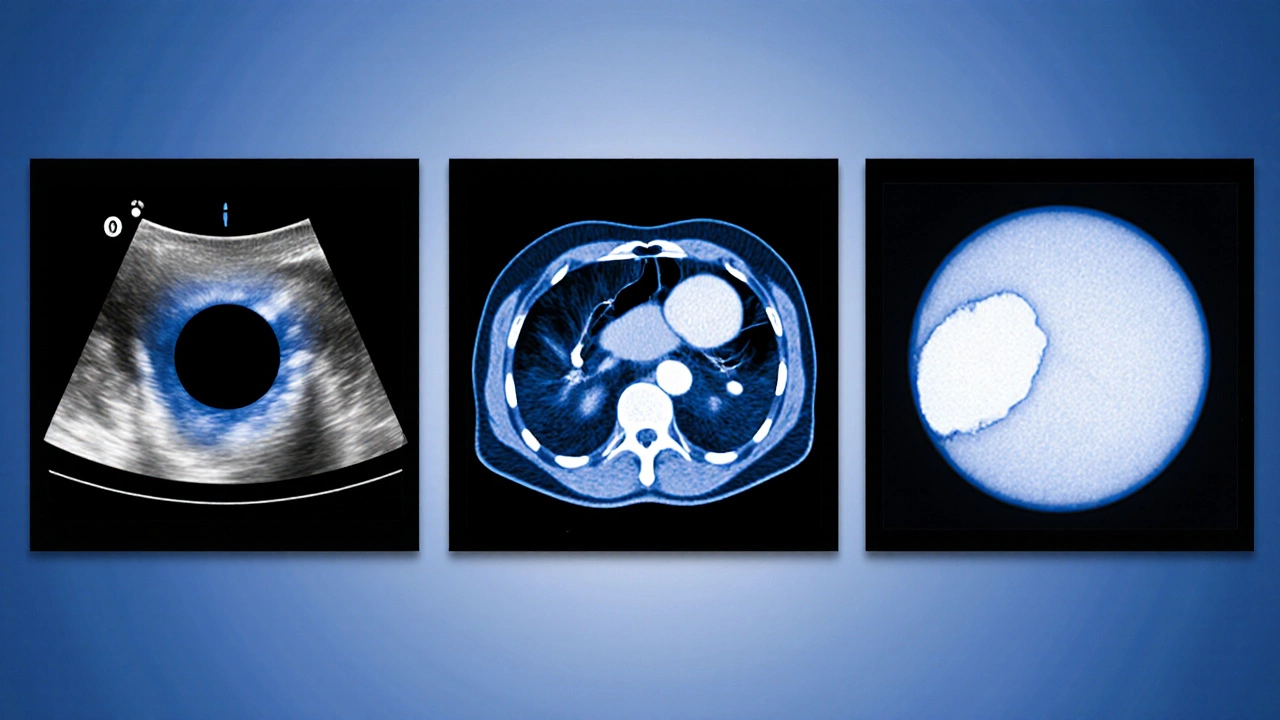

Самый надёжный способ отличить кисту от опухоли - визуальные методы. Давайте сравним их по доступности, стоимости и точности.

УЗИ | Ультразвуковые волны отражаются от тканевых границ | Высокая (почти в любой поликлинике) | 1 500-3 000 | 80‑90 % |

КТ | Рентгеновские лучи создают послойные снимки | Средняя (в региональных центрах) | 5 000-8 000 | 90‑95 % |

МРТ | Магнитные поля и радиоволны фиксируют различия в тканях | Низкая (только в крупных центрах) | 8 000-12 000 | 95‑99 % |

Для большинства наружных и мягкотканевых образований киста диагностика начинается с УЗИ, потому что он быстрый, безопасный и позволяет увидеть жидкостный компонент. Если результаты УЗИ неоднозначны, переходят к КТ или МРТ, которые дают более детальную картину структуры и сосредотачивают внимание на возможных стенках или кальцинатах.

Как интерпретировать результаты УЗИ, КТ и МРТ

Результаты обычно описывают три ключевых параметра:

- Размер и форма. Кисты обычно округлые или овоидные, с чёткой границей.

- Эхогенность (для УЗИ) или плотность (для КТ). Жидкость выглядит гомогенно темной (анэхогенной) на УЗИ и низкоплотной на КТ.

- Наличие сепараций или заболеваний стенки. Если внутри видны перегородки, это уже может быть сложная киста или опухоль.

Важно, что кисты могут иметь немного более плотный центр, если внутри присутствует кровь или протоплазм. В таких случаях врач сравнивает сигналы с типовыми изображениями в базе данных.